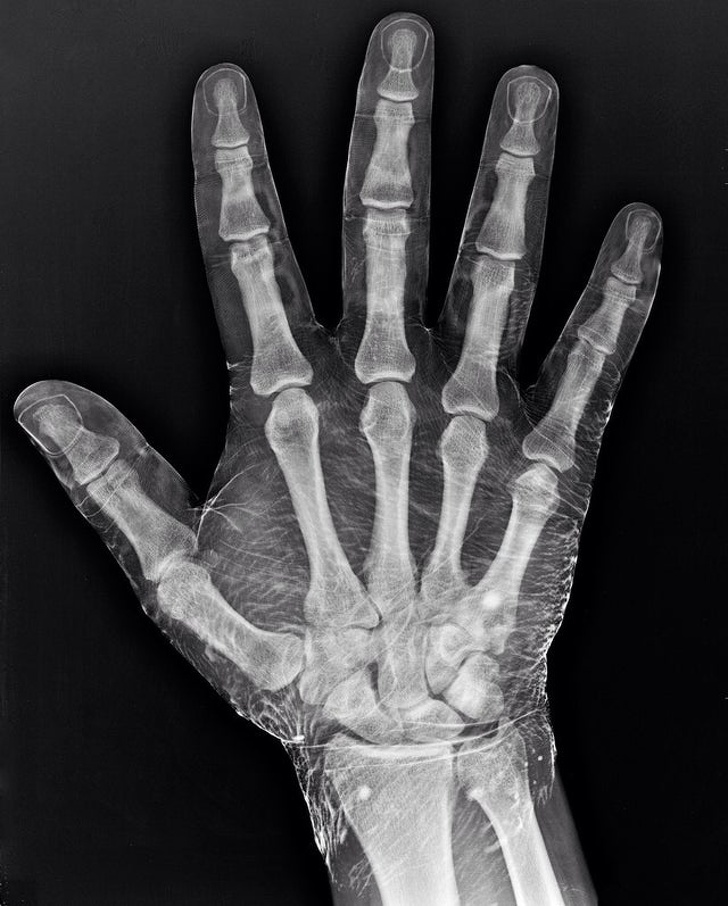

10, Így néz ki egy jódba mártott kéz röntgenfelvételen. A bőr felszívja a jódot és sokkal átláthatóbb lesz az egész felvétel.